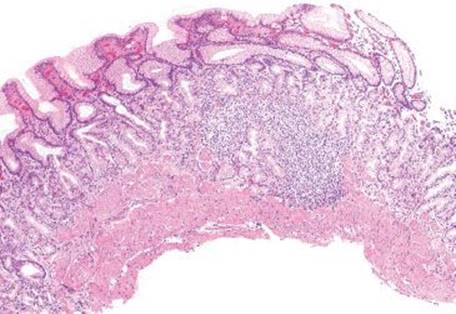

Lymphoid aggregates subpattern is defined as the presence of benign lymphoid aggregates or lymphoid follicles involving the mucosa (Figs. 2.114–2.119). This subpattern is perhaps the least specific of the chronic gastritis subpatterns, but one of the most common, and most easily identifiable at low power. Lymphoid aggregates can be seen in any form of chronic gastritis, regardless of etiology, and are commonly associated with EMAG’s Helicobacterinfection and treated Helicobacter. These aggregates can be antral predominant, or extend into the gastric body and fundus in EMAG.

Figure 2.114 Chronic gastritis pattern, lymphoid aggregate subpattern, late EMAG. At scanning magnification, the prominent lymphoid aggregate is eye catching. Lymphoid aggregates are not always helpful in differentiating AMAG from EMAG. For example, this lymphoid aggregate is seen in the body compartment, but the superficial band-like inflammatory infiltrate (arrowheads) indicates this is most likely Helicobacter related (late EMAG).

Figure 2.116 Chronic gastritis pattern, lymphoid aggregate subpattern, AMAG. At scanning magnification, a prominent lymphoid aggregate is present in this body biopsy. Given the location of injury and the combination of background intestinal metaplasia and the total lack of oxyntic glands, the etiology is likely AMAG.

Figure 2.117 Chronic gastritis pattern, lymphoid aggregate, AMAG. Another example of prominent lymphoid aggregates at scanning magnification. Although this biopsy is labeled “body”, no oxyntic glands are present.